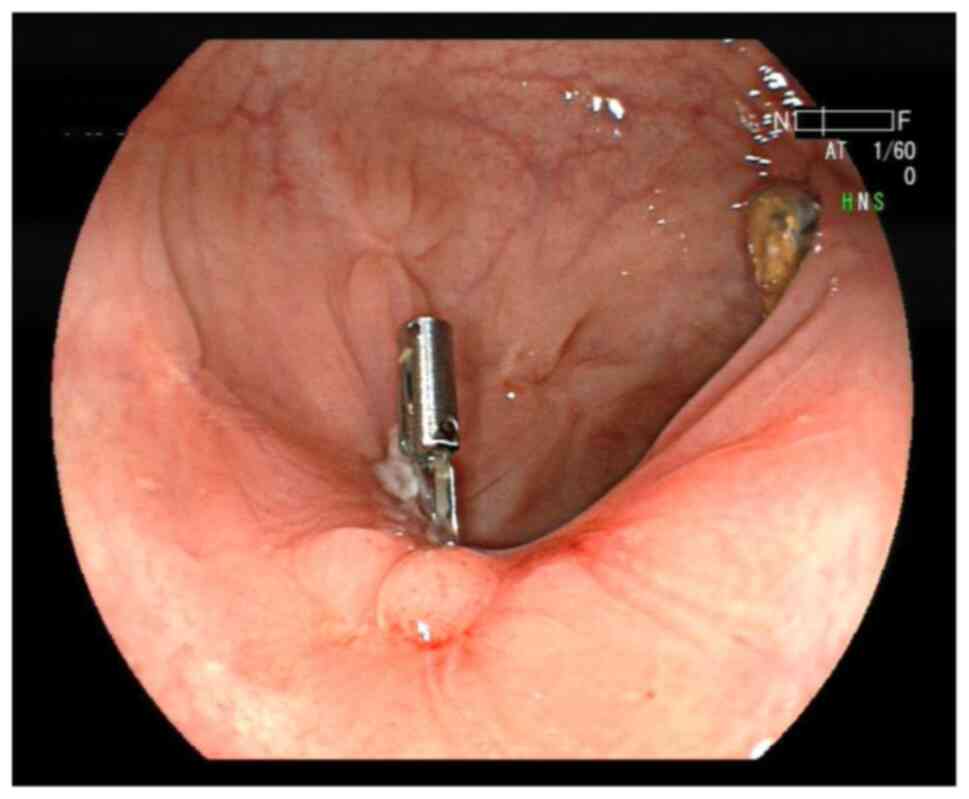

Figure 1

Endoscopic ultrasonography showed that the rectal submucosa had a low echo convex lesion, 0.6-0.8 cm in size. The blue box indicates the location of the convex lesion.